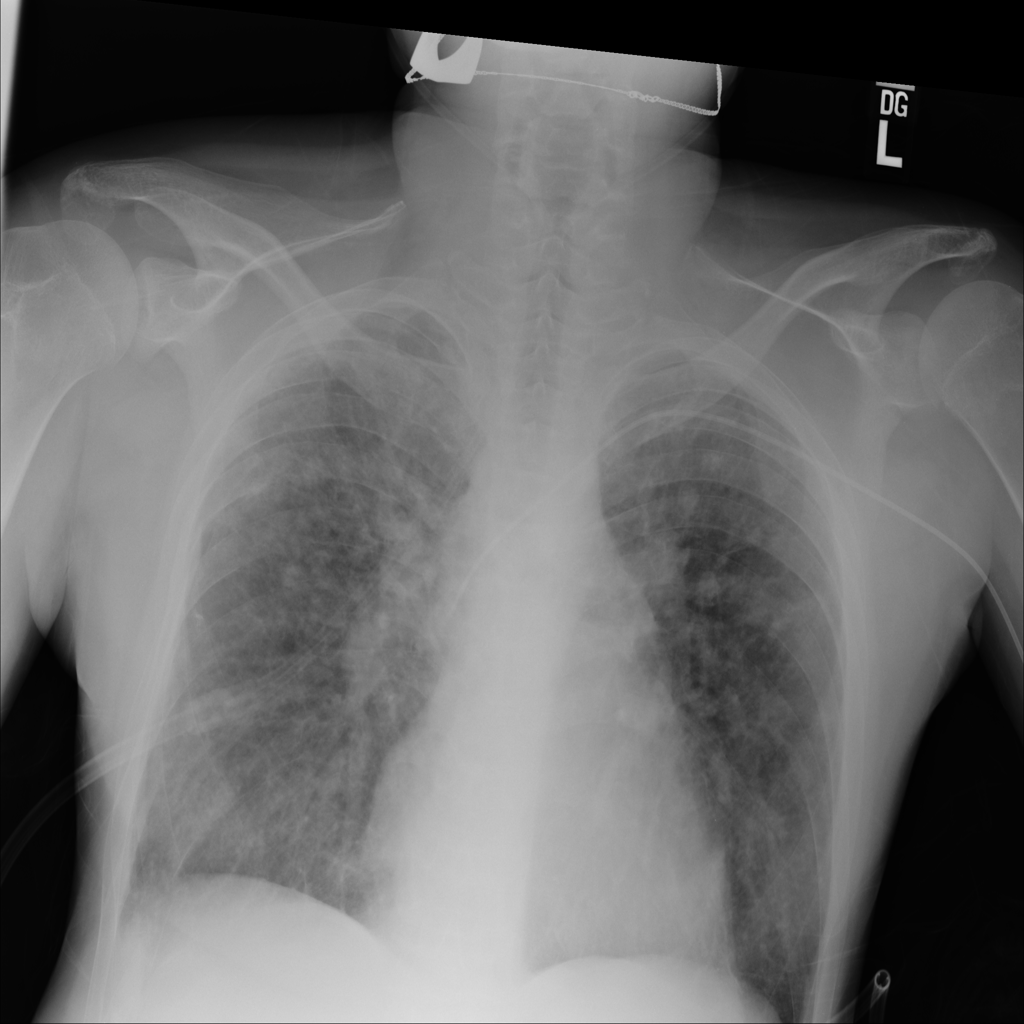

PAT-4639 · IMG-013Pneumothorax

PAT-4639 · IMG-013

AP